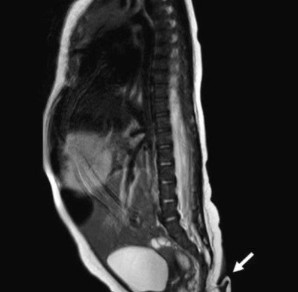

Dr. Josue Rueda, Meksika'da bir ilk olan kuyruklu bebeğin kuyruk sokumundan çıkan deri parçasını, '3 ila 5 mm çapında ve 5,7 cm uzunluğunda, yumuşak, ince tüylerle kaplı ve sivri bir uca sahip.

Acı çekmeden pasif olarak hareket ettirilebiliyor ancak spontane hareket gösteremiyor' sözleriyle anlattı.

Yapılan araştırmaya göre, omurgası düzgün şekilde oluşmadığı için Meksikalı bebekte kuyruk oluştuğu açıklandı.

Beyin, kalp, işitme ve idrar testlerine giren yeni doğmuş bebeğin sağlıklı olduğu ve kuyruk sıkıştırıldığı zaman ağlamaya başladığı belirtildi. İlginç olayın ardından kuyruk ekipler tarafından incelendi ve yumuşak dokulu yapının atardamar ve toplardamarlara sahip olduğu belirtildi.